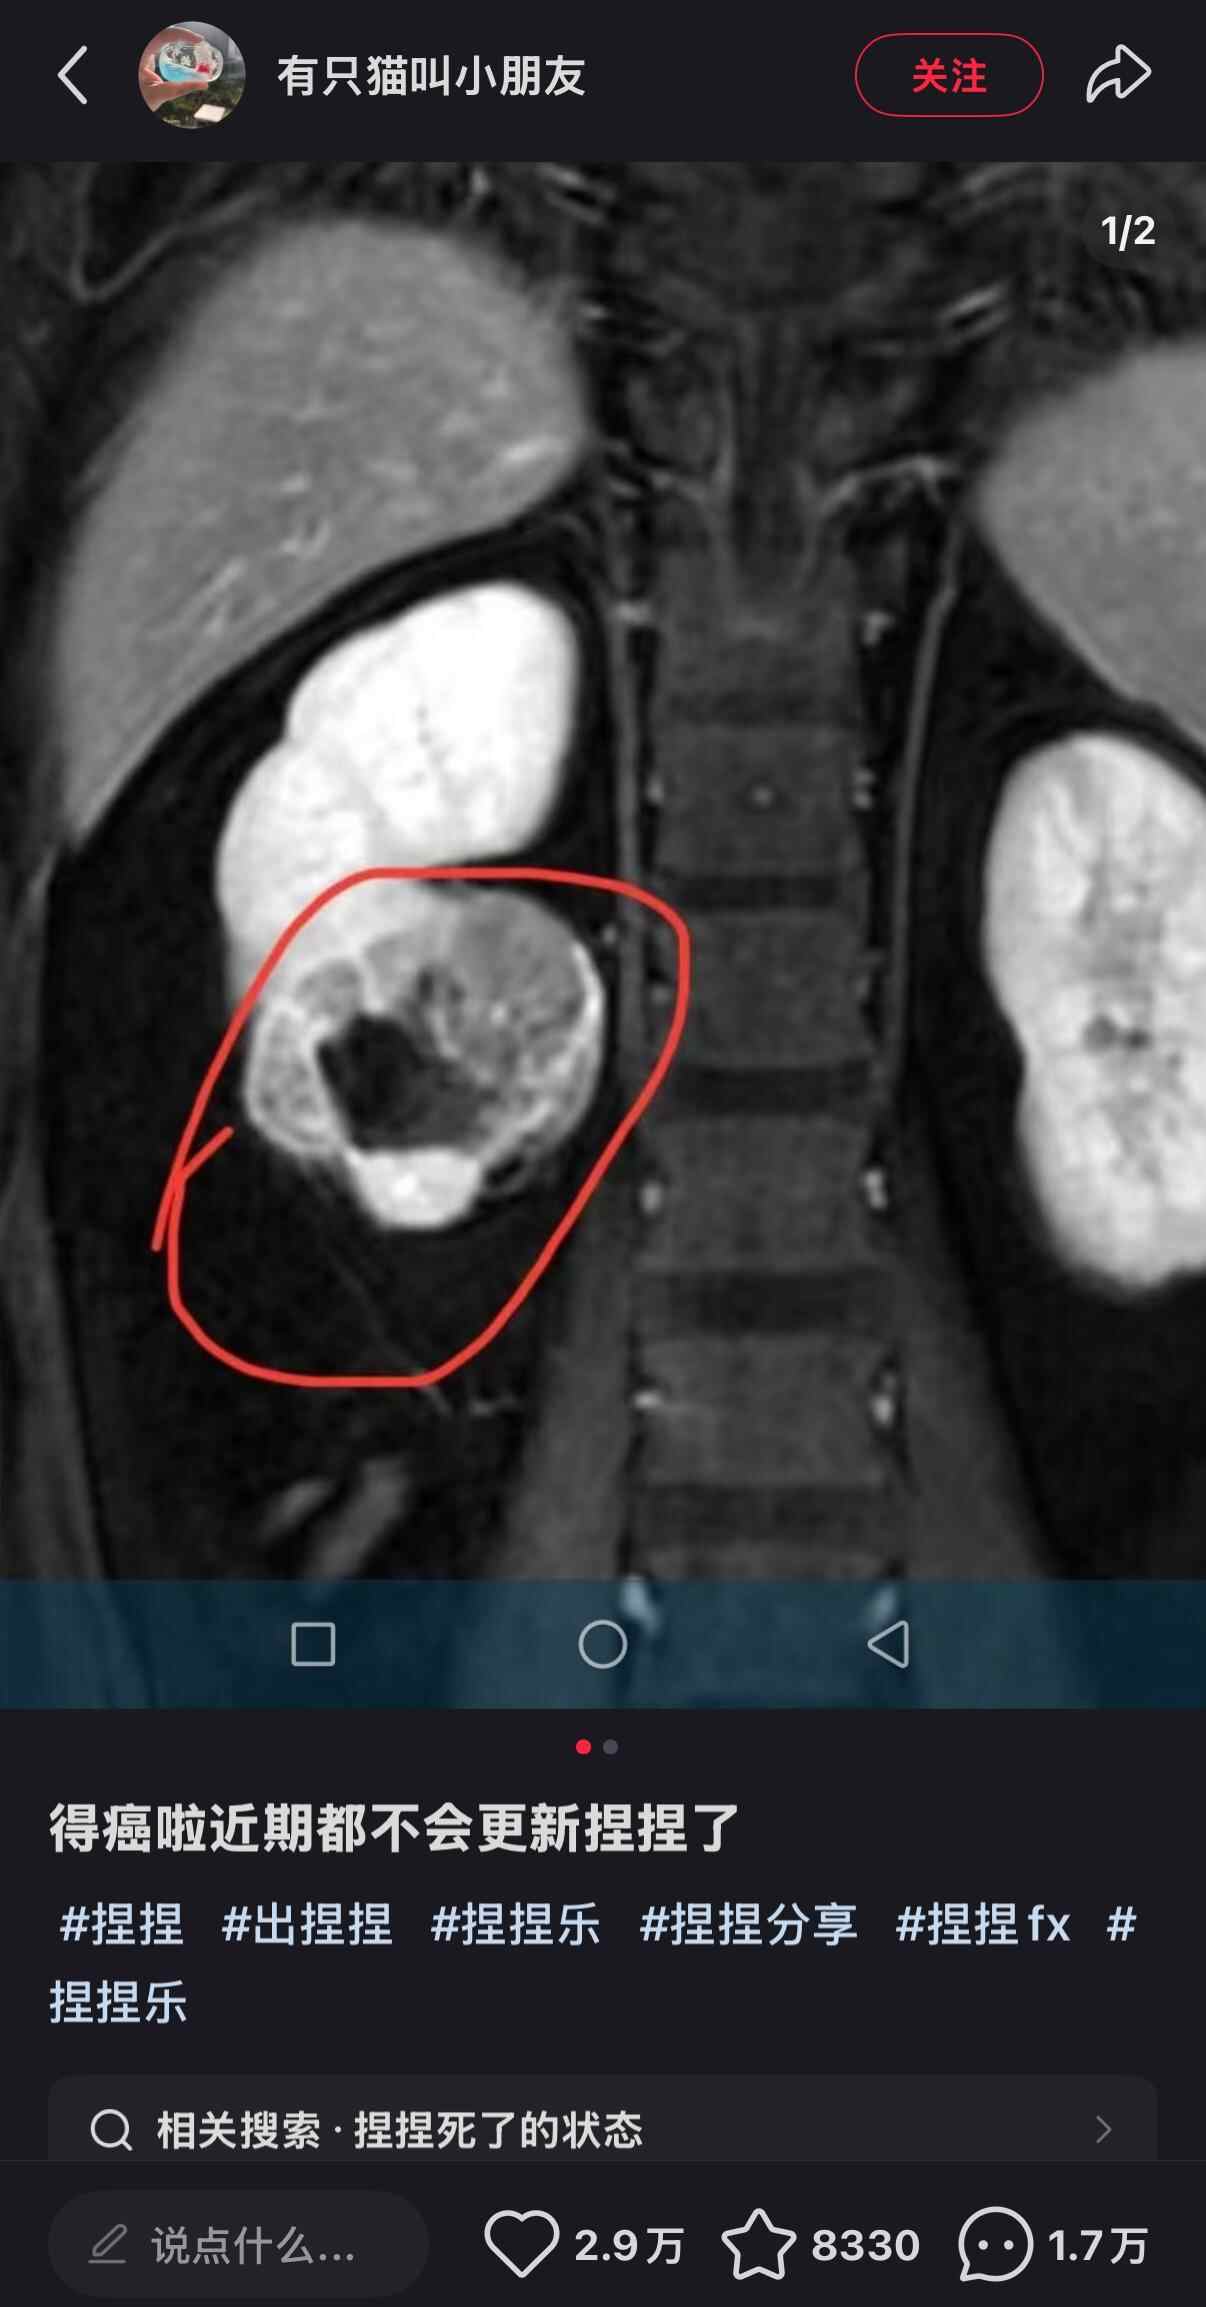

近日,解压玩具博主“有只猫叫小朋友”在社交平台宣布罹患癌症并暂停更新视频。虽然未透露其患病原因,但有网友猜测,是否与其常揉捏“捏捏”玩具有关。由此,也引发了公众对“捏捏”玩具安全性的担忧。